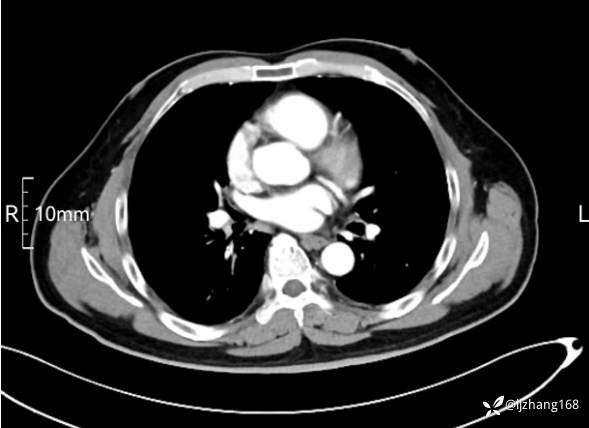

中年男患,右肺团片影,炎症0R肿瘤?

辅助检查:糖化血红蛋白12.3%。肺炎支原体IgG、IgM、呼吸道合胞病毒均未见明显异常。胸部CT:右肺上叶阻塞性肺炎。